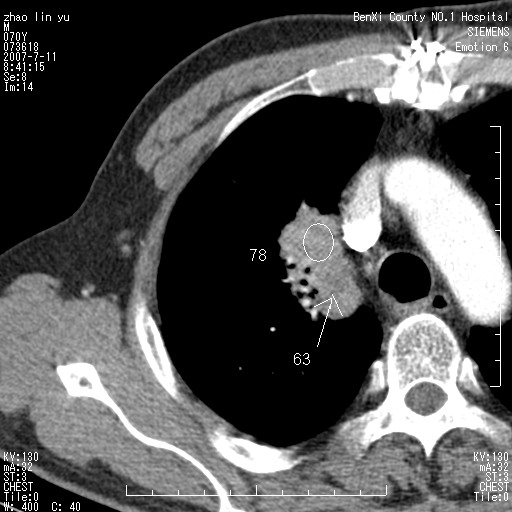

以下是引用王靖旗在2007-7-10 17:12:00的发言:[br] 男、70、咳嗽两个月,半年前换瓣手术,胸片未见异常,于昨天行x片发现右肺上野大片影,行ct扫描,这里是减薄图像,余肺正常。明天晚上会有增强扫描片,到时我会上传。[br][br] 冠状位请大家细看,应该是有意义的,[br][br] 请大家先看平扫发表意见。[br][br]

以下是引用zhangzhongshou在2007-7-10 21:43:00的发言:[br]右肺上叶周围型肺癌,以孤立型细支气管肺泡癌可能性大。